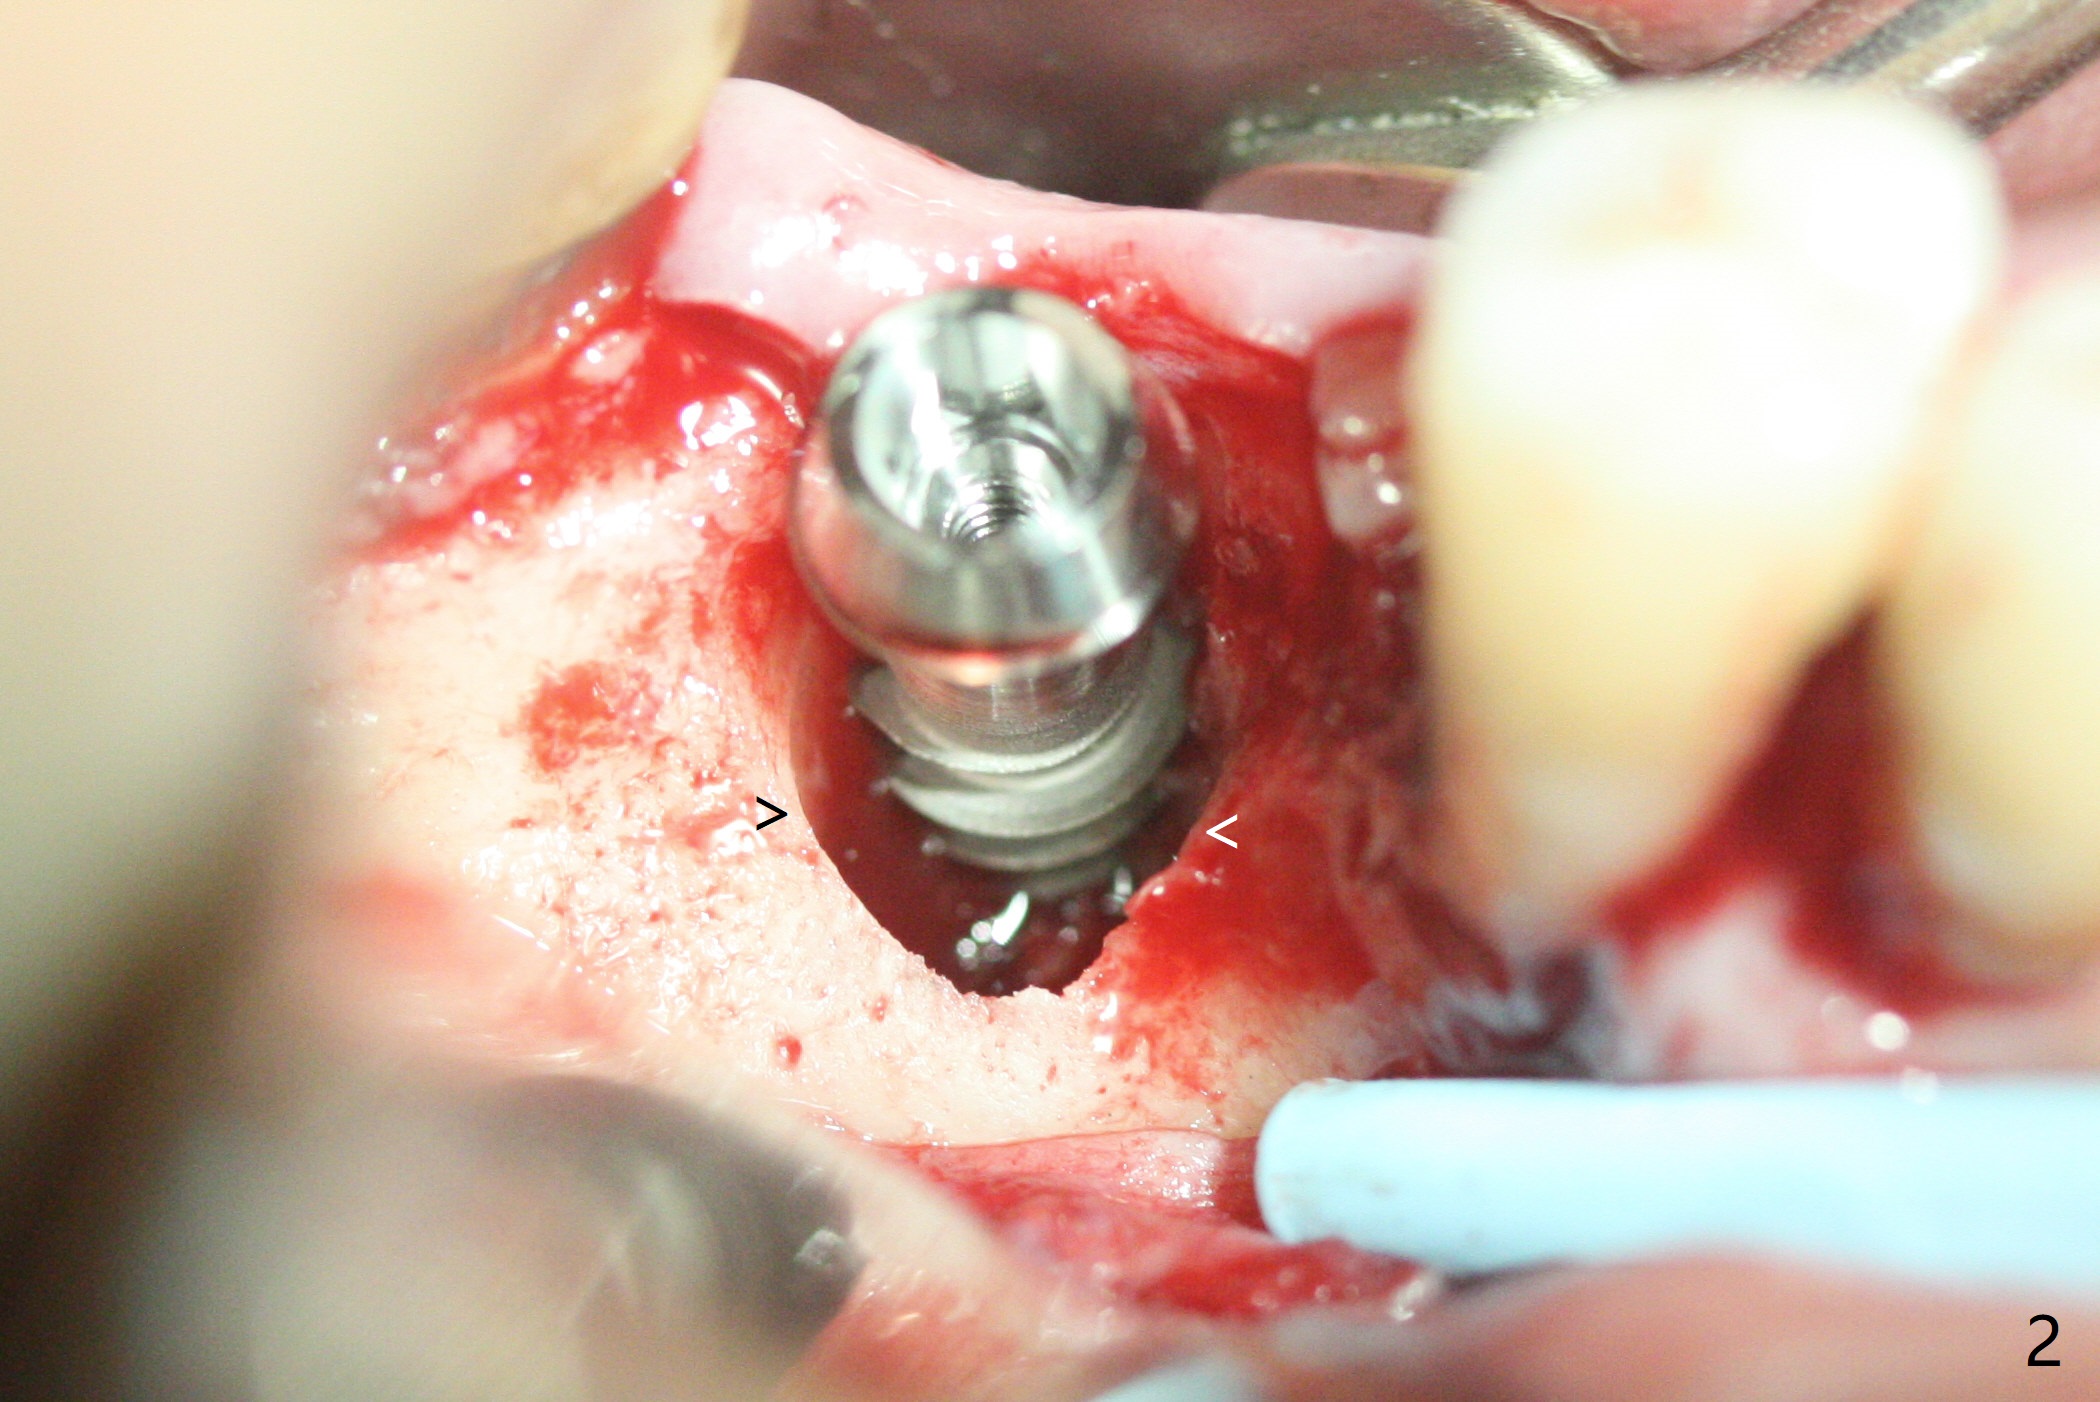

A 5x12 mm SM implant with periimplantitis at #30 is removed with a 5/6 mm trephine bur, small elevator and implant driver. A 3.8 mm Magic drill is used to start a new osteotomy in the lingual wall of the old one free hand. With the final drill (4.8x13 mm), a 5x11(3) mm Magicore is placed (Fig.1-4). The large buccal gap (Fig.2 arrowheads) is filled with allograft (Fig.3 *). The latter is covered by PRF, followed by suture. Periodontal dressing is applied around the 4.2x3 mm solid abutment and the coronal portion of the Magicore (Fig.4 <). The green outline in Fig.5 (CT coronal section) represents a new 5x10 mm implant (design), while the thick red line is approximately the long axis of the new implant. The implant heals in spite of buccal recession. Impression is taken with placement of a 4.3x5 mm solid abutment 4.5 months postop (Fig.6). Take follow-up CT to determine buccal bone formation.